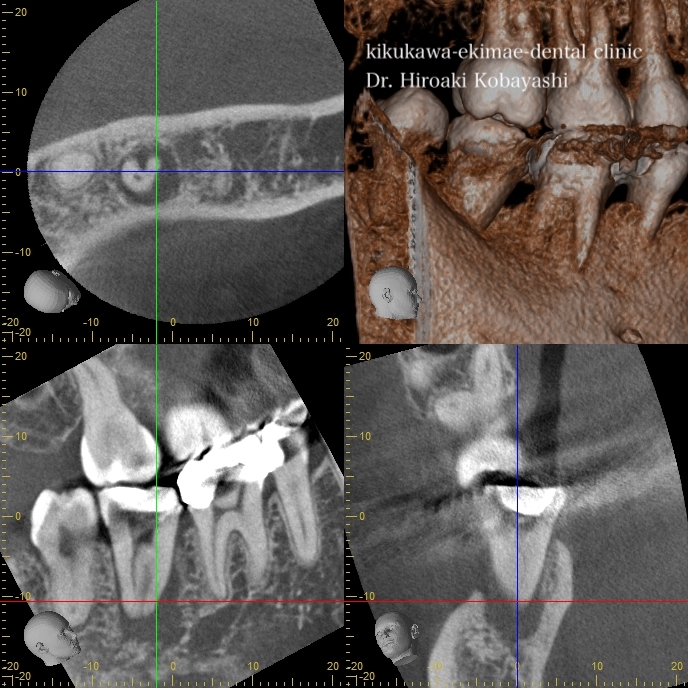

根管治療後の骨の再生

神経が感染し根の尖端の骨を溶かしています。この歯の中の感染物質を除去し、尖端の骨の再生を促す治療を感染根管治療と言います。この病気の厄介なところは、歯周病と同様に痛みが出る場合もありますし、痛みがない場合もあります。

精密根管治療にて細菌を除去し、根の薬を入れた直後はまだ完全な骨の再生は起こりません。

6ヶ月〜1年ほどかけて骨の再生が起こります。適切な時間を確保し、顕微鏡やラバーダムをちゃんと使用した、精密根管治療により根の中の細菌感染がなくなれば後は体が勝手に治してくれます。あとは、被せ物をきちんと入れる事と、セルフケアの徹底にて長期の保存を目標とします。